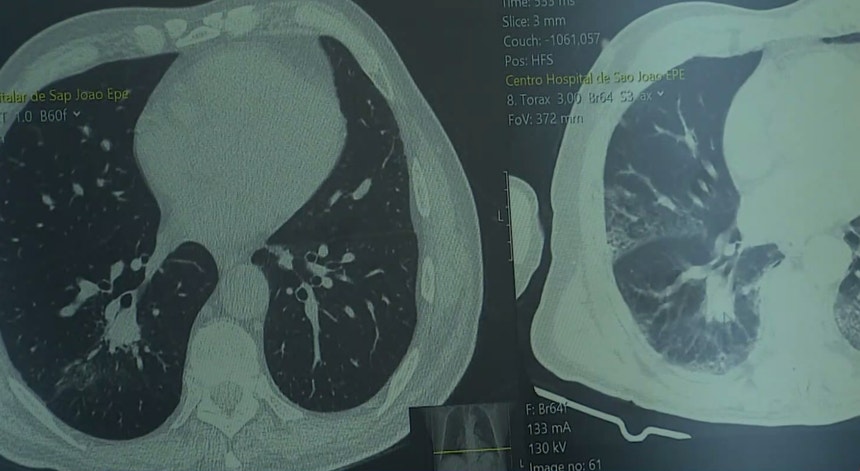

Cancro do pulmão provoca 11 mortes por dia em Portugal

Em pleno Dia Mundial do Cancro do Pulmão os especialistas confessam-se aliviados pelo concretizar de um rastreio que pode reduzir em 20% os óbitos do tumor mais mortal.